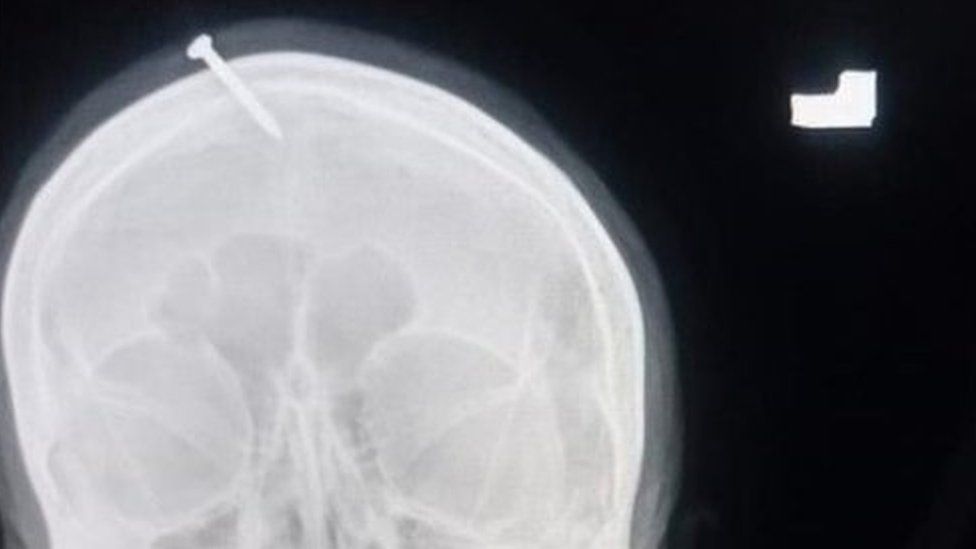

X光片显示,5公分长的钉子刺进了妇女的额头上方,但幸好没刺中她脑部。

医生说,这钉子是用铁锤或其他重物敲进她头部。

海德医生指出,钉子已经深入到受害者的头骨中,“(她的)家人说,她在家里就失去了知觉。家人试图在家里把它取出来,但做不到。”